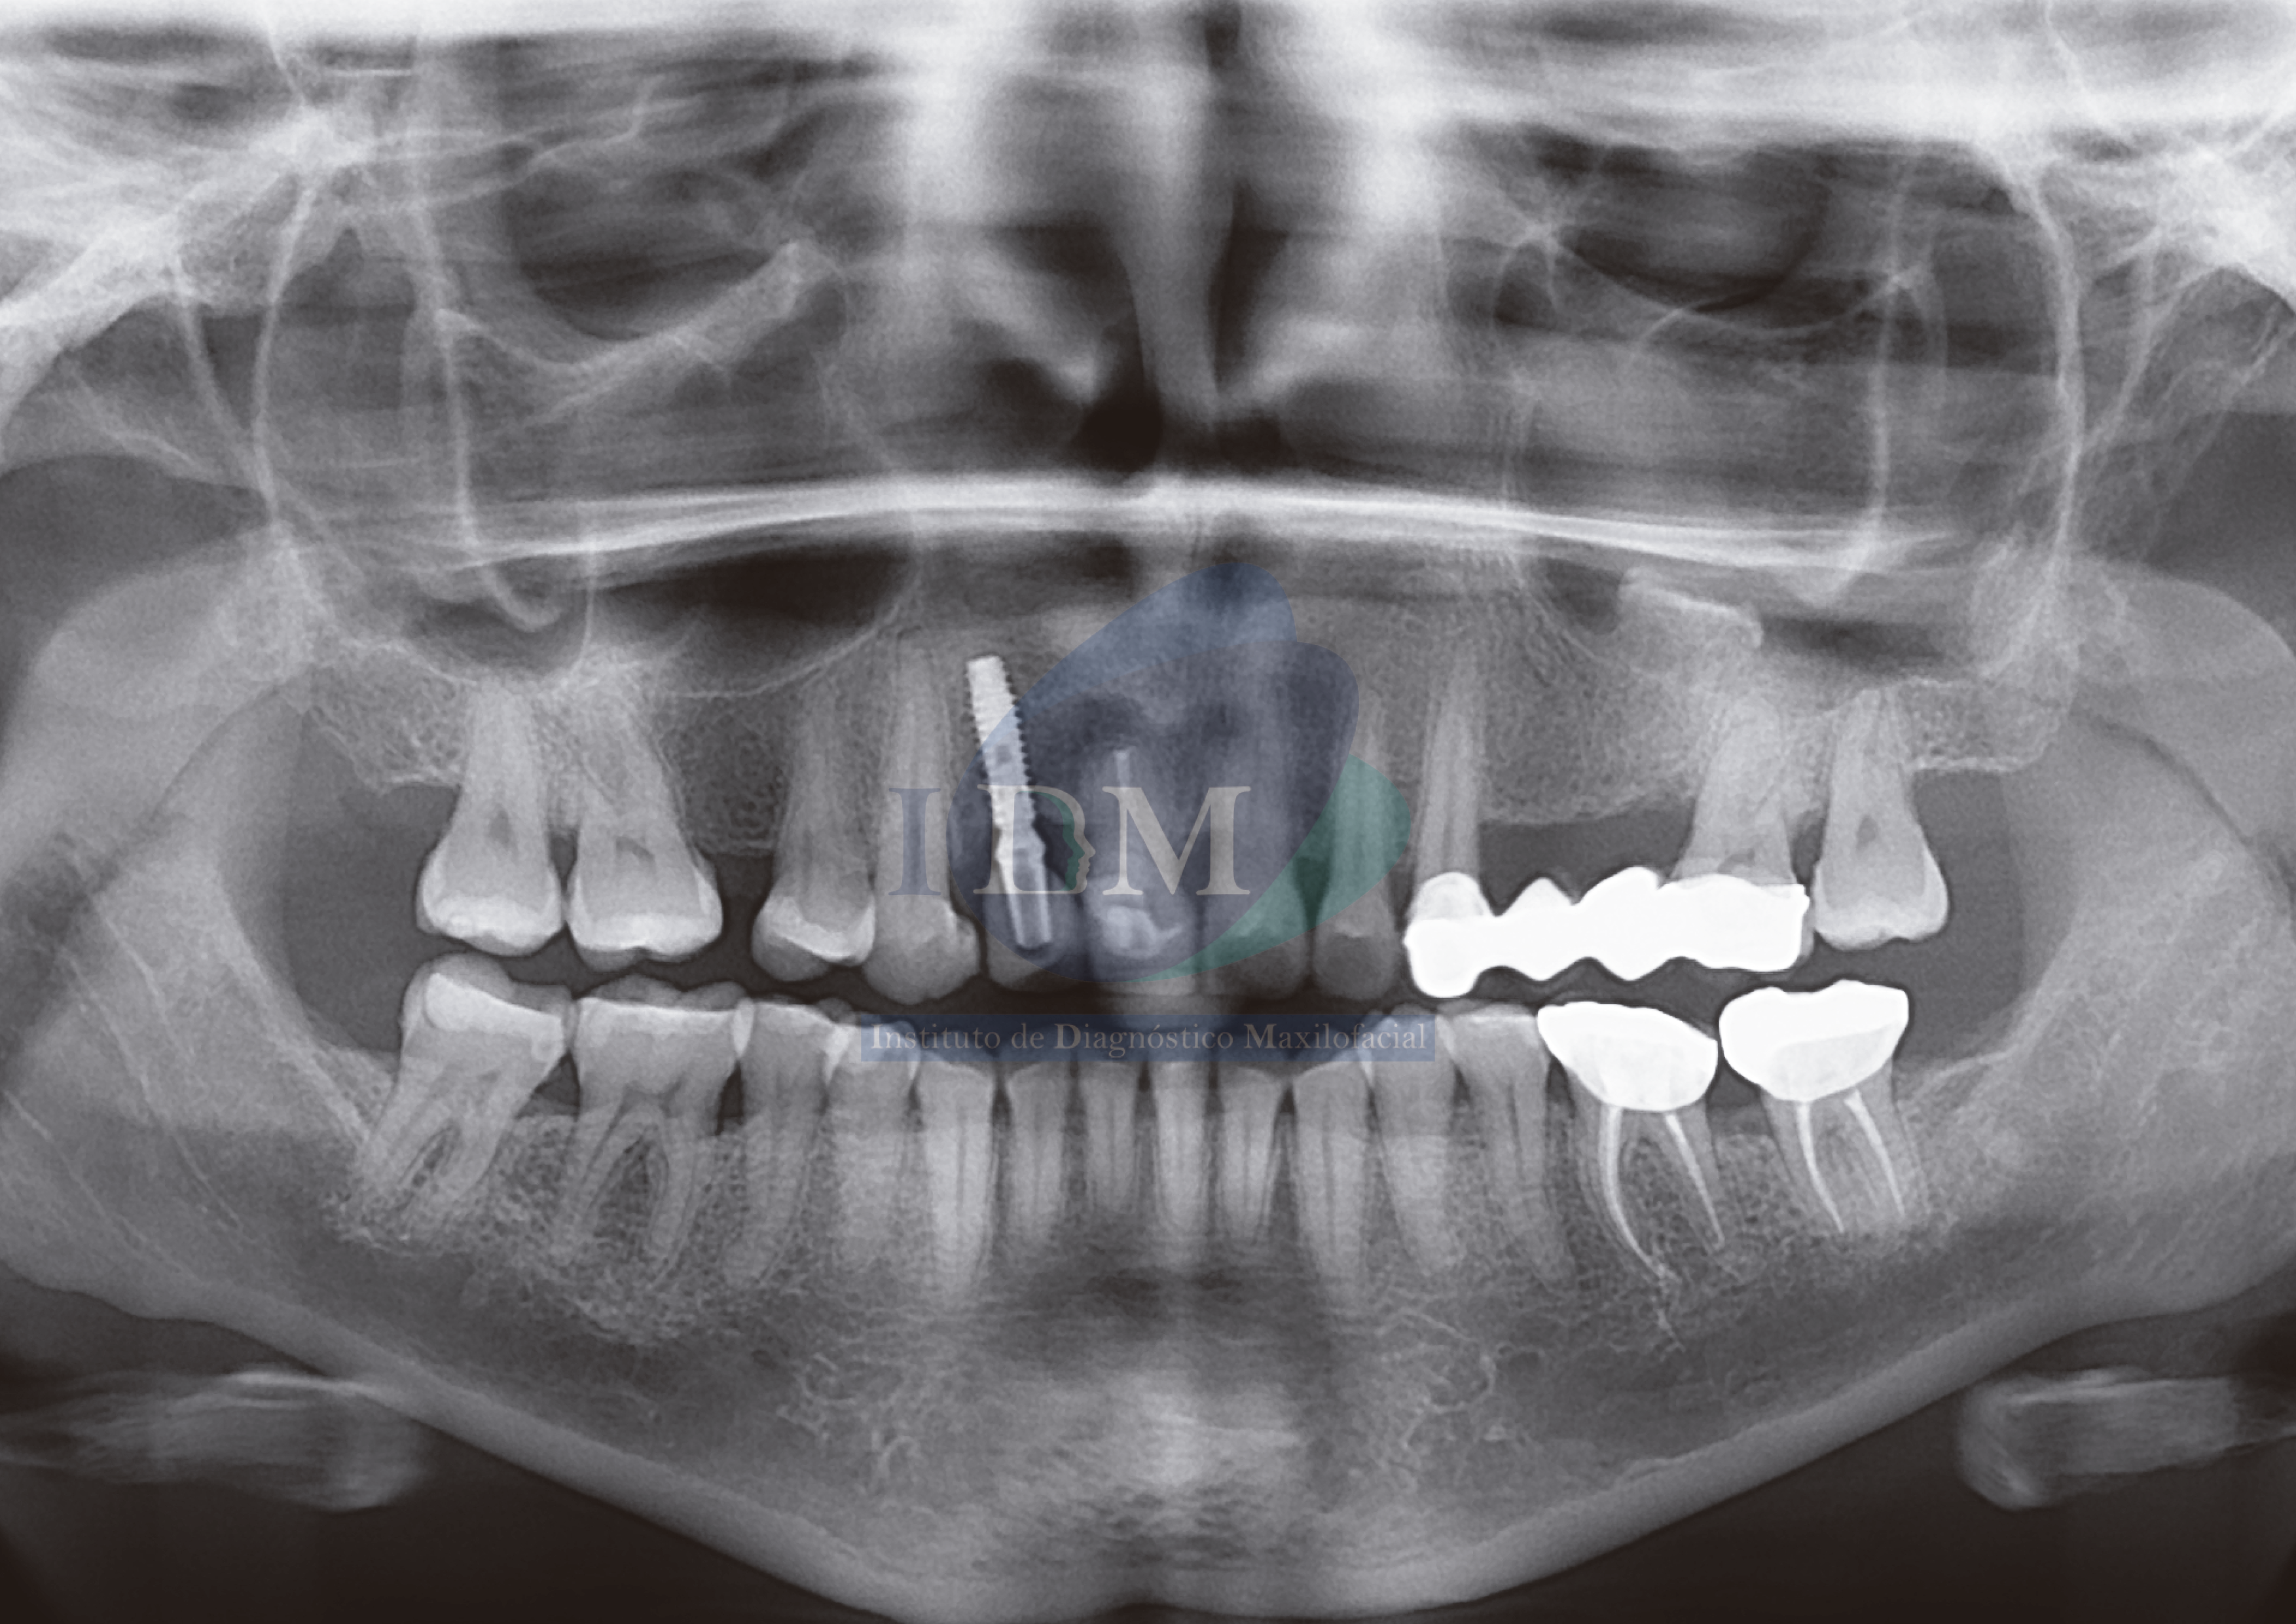

En la radiografía panorámica se observa una radiopacidad irregular en piso del seno maxilar izquierdo que se extiende desde la cortical ósea del piso hacia el antro sinusal a nivel de la zona de pieza 25 y 26.

Radiografia Panorámica